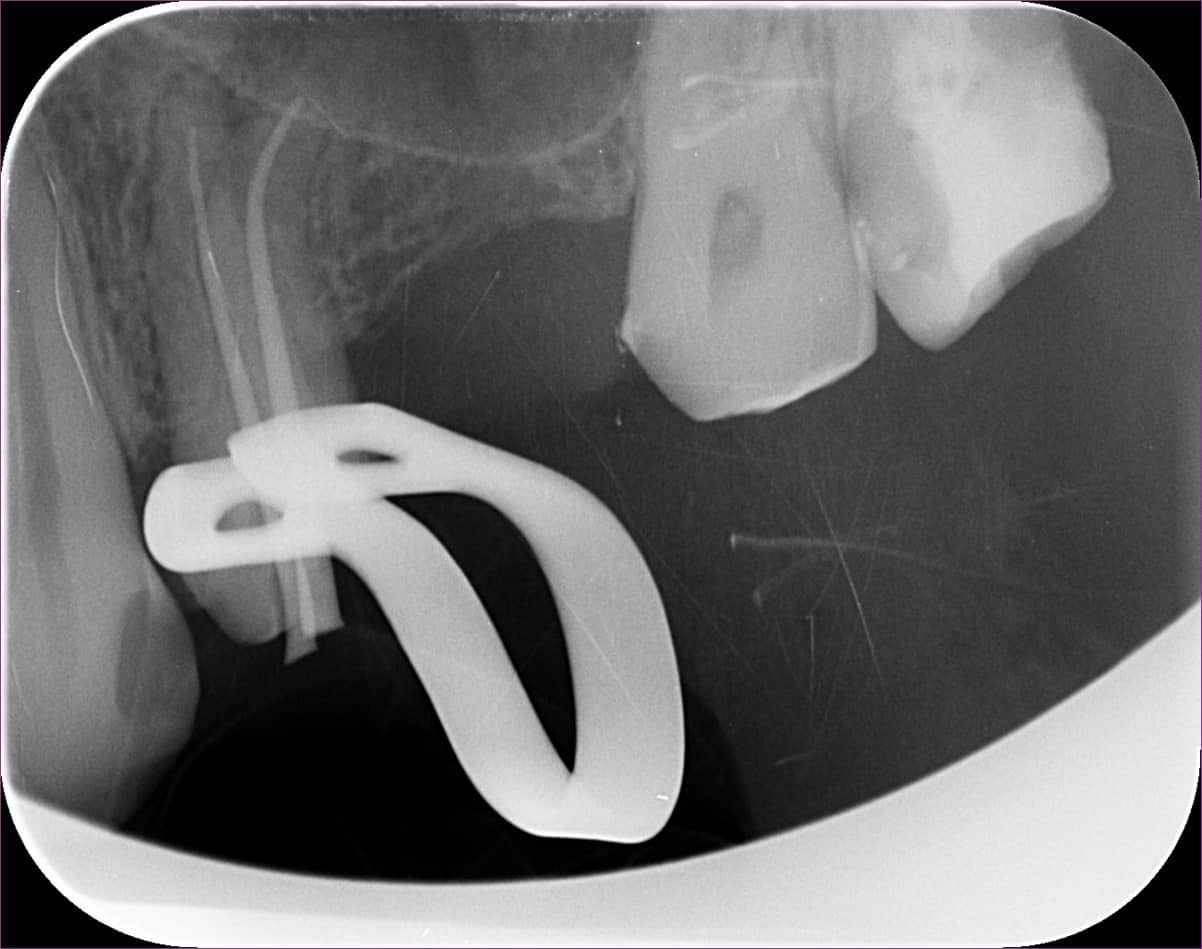

Sajnos a csiszolást követően a négyes fog egyre érzékenyebb lett, így a gyökérkezelés mellett döntöttek. Ám a csatornák görbeségét látva a kiinduló röntgenfelvételen (lásd fentebb), hagyományos módszerrel a kezelésbe nem mertek belevágni. A megoldás tehát a mikroszkópos gyökérkezelés lett.

A mikroszkópos gyökérkezelés menete szerint haladtunk. A fog kinyitása után a csatornákat a látható görbület miatt óvatosan, különleges technikával dolgoztuk fel. Már a kezelés elején érzékelhető volt, hogy a két, egyébként külön kijárattal rendelkező csatorna között van kapcsolat. Az egyik csatornába egy speciális szívóberendezést helyezve a másik csatornából is sikerült eltüntetni a folyadékot.

Közvetlenül a gyökértömés előtt a majdani gyökértömő „pálcikákkal” készült röntgenfelvételen ellenőriztük, valóban jó helyen vagyunk-e, és az elektromos bemérő készülékünk segítségével jó hosszokat sikerült-e megállapítanunk.